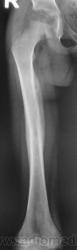

Пожалейте ребенка, не надо томографировать. Все укладывается в норму. Просто головка еще маленькая, а медиально - это шеечная шпора. Уж если не верите, снимите оба сустава одновременно.

Вот еще такой возраст.

И всё-таки не совсем то. На рентгенограмме представленном Ola-la всё кристально чётко и понятно. Даже тормозным взрослым рентгенологам. А вот на картинке Главного рентгенолога туманно… не до конца ясно, что в нижнем отд. впадины. Кстати у Валентина Львовича сегодня день рождения, как и у меня. Я позравляю!

Интересная дискуссия. Жаль с опозданием увидел (однако же, много времени уходит, пока всё на сайте просмотришь). На мой взгляд, патологии головки нет, без фрагментации, проекционно пересекается с тенью обызвествляемого Y-хряща. Под головкой медиально, несомненно, есть остеопороз, придающий нечеткость картине. Впрочем, регионарный остеопороз имеет место вследствие закономерной атрофии после иммобилизации. Сюда же наслаивается субстрат т.н. фигуры серпа, еще не оформленный. Впадина нормальная. Кость срослась - замечательно, всем бы такие результаты. Реабилитация обязательна.